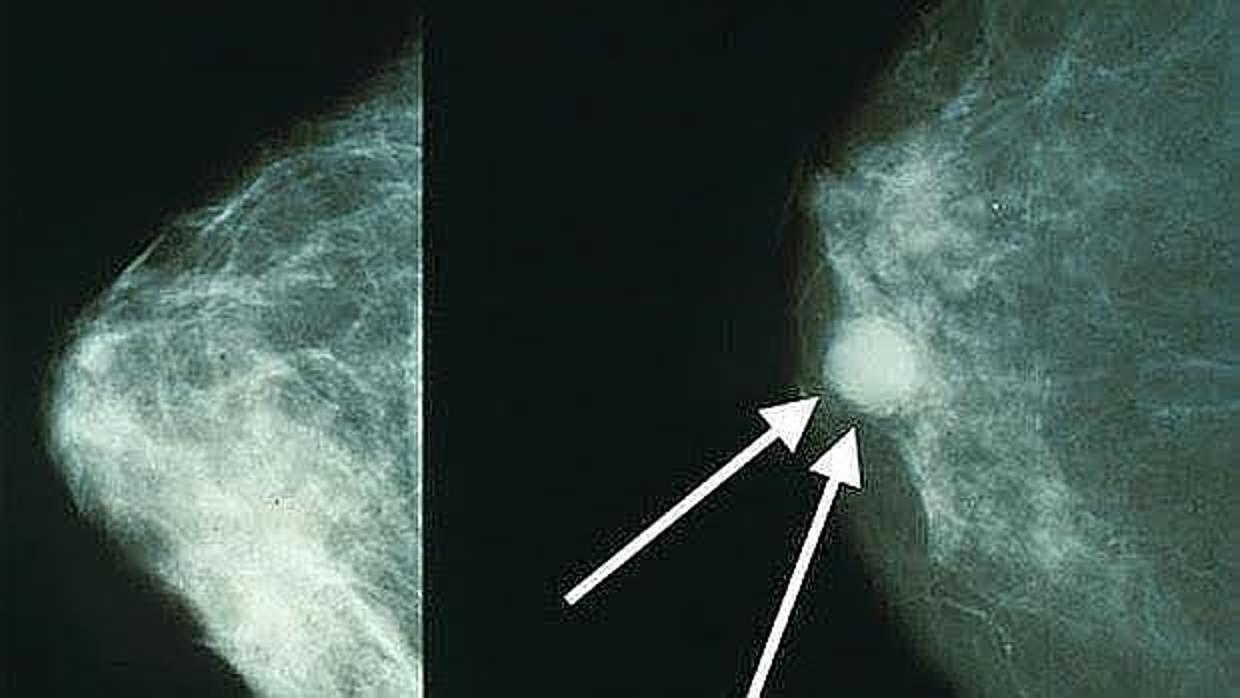

Cáncer de mama ARCHIVO